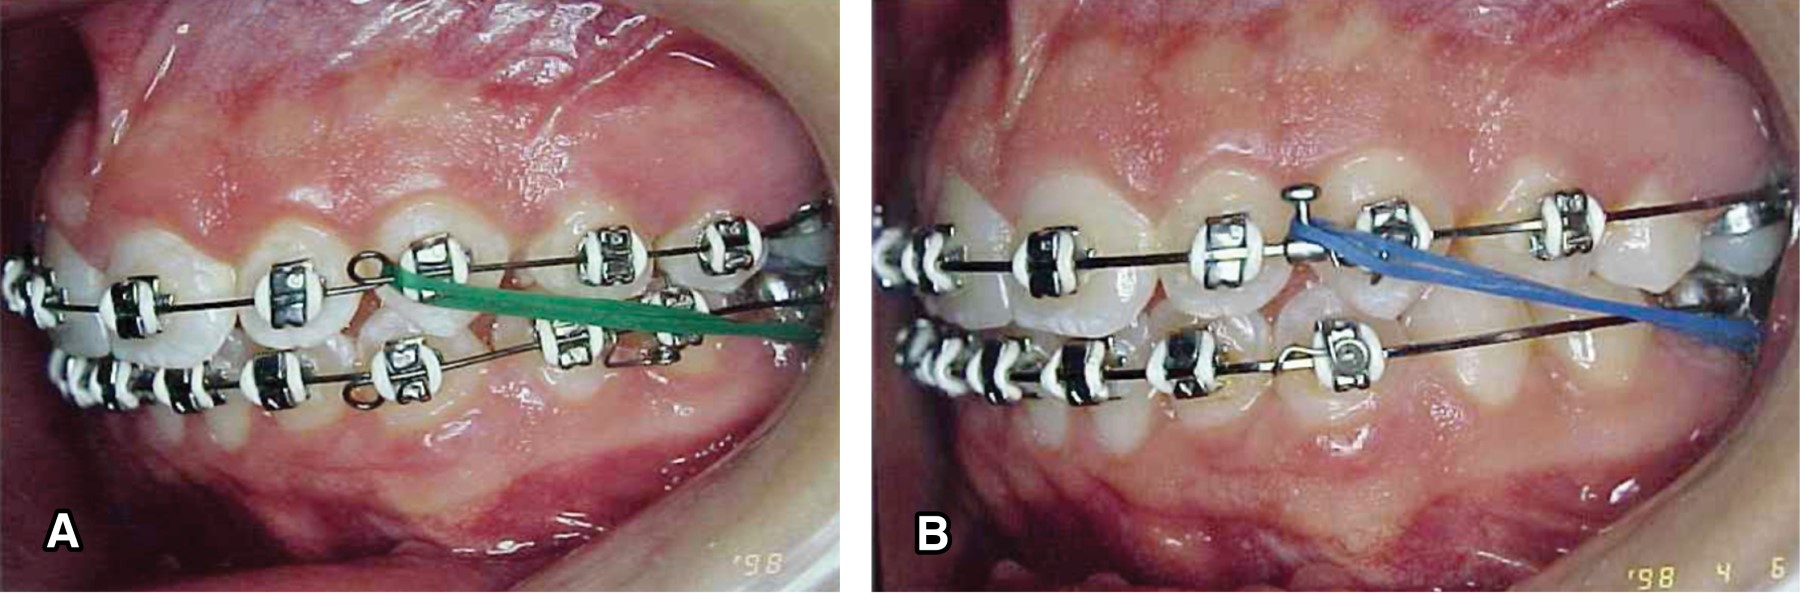

RETRACTION OF THE ANTERIOR SEGMENT

Undoubtedly one of the crux movements in orthodontics that is closely related to the anchorage is the retraction of the anterior segment at the time of space closure in extraction cases. It is very common that for space closure the distalization of the canines is performed first followed by the retraction of the four incisors with different strategies and archwire designs, mostly with rectangular or square wires (Figure 3), different authors such as Wick Alexander recommend the intensive use of the extraoral archwire in these phases6 this type of mechanics is done just to conserve the posterior anchorage since it is not easy to retract six teeth together relying only on the first molars, not to mention the unsightly phase the patient goes through when the canine is retracted first. (Figure 4) in the Tip-Edge system thanks to the design of the bracket (Figure 5) created for space closure, it is possible to bring distally the six anterior teeth together at a considerable speed,7 or even eight teeth when the second premolars are extracted or also to retract ten teeth together, in cases of extraction or absence of the first molars and retract from the second premolar to the second premolar together without the need of additional anchorage (Figure 6), this is a great advantage at a biomechanical and esthetic level.